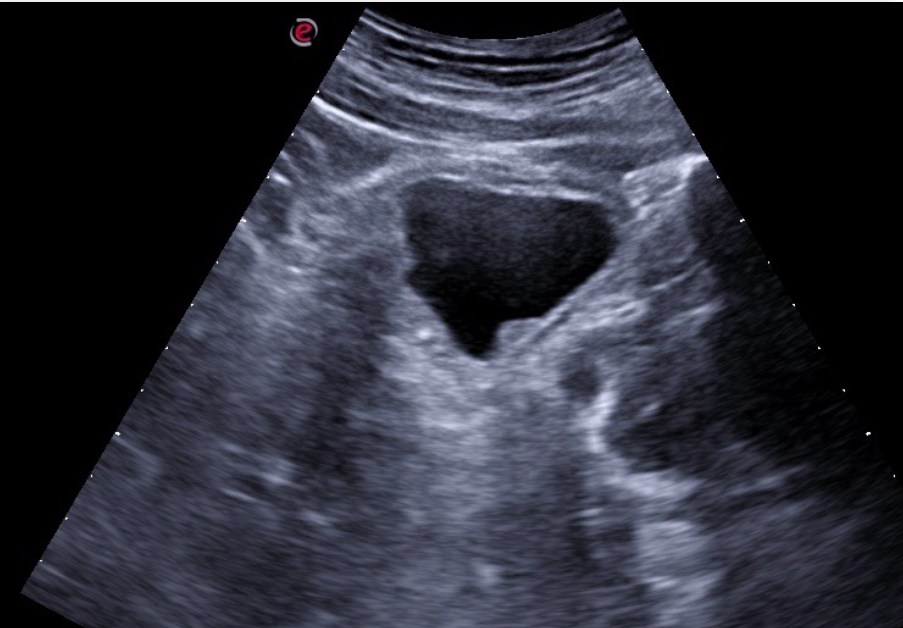

Expondremos la utilidad de la EC como herramienta en el manejo de los pacientes con diferentes tipos de dolor que atiende el Médico de Familia en las consultas diarias, urgentes, e incluso en los domicilios, en diversos escenarios clínicos a los que podemos enfrentarnos en nuestra práctica clínica habitual, desde un dolor visceral (abdominal, torácico, urológico o ginecológico), un dolor músculo-esquelético (traumático o no, con sospecha de fractura u osteoartrósico incapacitante), un dolor vascular (sospecha de trombosis venosa profunda, trombosis arterial aguda, aneurismático); ayudando a obtener una información crucial con un método no invasivo que nos ayudará a reducir la incertidumbre y orientar mejor el diagnóstico de nuestros pacientes e incluso nos podrá ser muy útil como herramienta con fines terapéuticos como en el caso de las infiltraciones ecoguiadas.